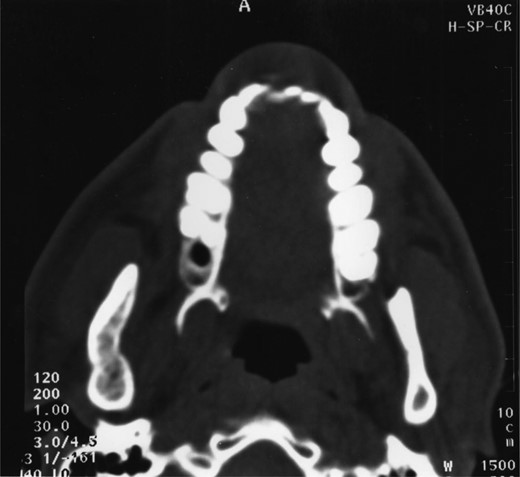

Plain films along with CT scan, with 3 mm slices, were performed a further year later and showed good bone regeneration in the right ramus and condylar neck (Figs 4 and 5). No evidence of cystic recurrence was seen and no abnormalities within the adjacent soft tissues. High-resolution magnetic resonance imaging also confirmed the absence of cystic remnants. The patient has now been reviewed for 5 years and there is no evidence of recurrence.